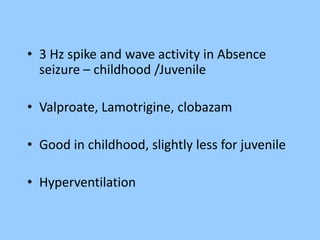

1. The document discusses EEG patterns and findings in various neurological conditions seen in children. It includes descriptions of normal EEG findings as well as abnormal patterns seen in conditions like absence seizures, West syndrome, benign childhood epilepsy with centrotemporal spikes, Lennox-Gastaut syndrome, non-convulsive status epilepticus, subacute sclerosing panencephalitis, and herpes encephalitis.

2. Case studies are presented with clinical histories and EEG findings to illustrate different pathologies. Treatment options are also mentioned for many of the conditions.